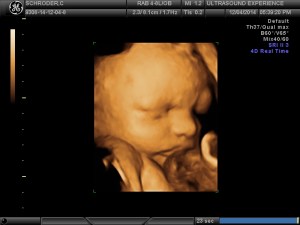

we saw you today

…and it was amazing. As if we couldn’t love you anymore…we do. Seeing your precious face in 4D was an incredible experience. We saw your facial features and they are so defined! You already have expressions that resemble mine and your dads and it was so awesome to see that 🙂 You are unbelievably adorable with a full head of hair, pronounced nose and mouth and scrumptious cheeks. You were very active during the ultrasound and were wiggling around and moving your tiny hands and feet non-stop. You smiled for us and even threw up a peace sign…just like your mama 🙂

It makes waiting another 9 weeks (give or take) even harder because we just want to meet you now!

All the grandparents joined us at the 4D & they are so in love with you also. We went out after to celebrate at an amazing sushi & robata japanese restaurant and you may have tasted the way too spicy shishito pepper I ate, sorry baby 😦